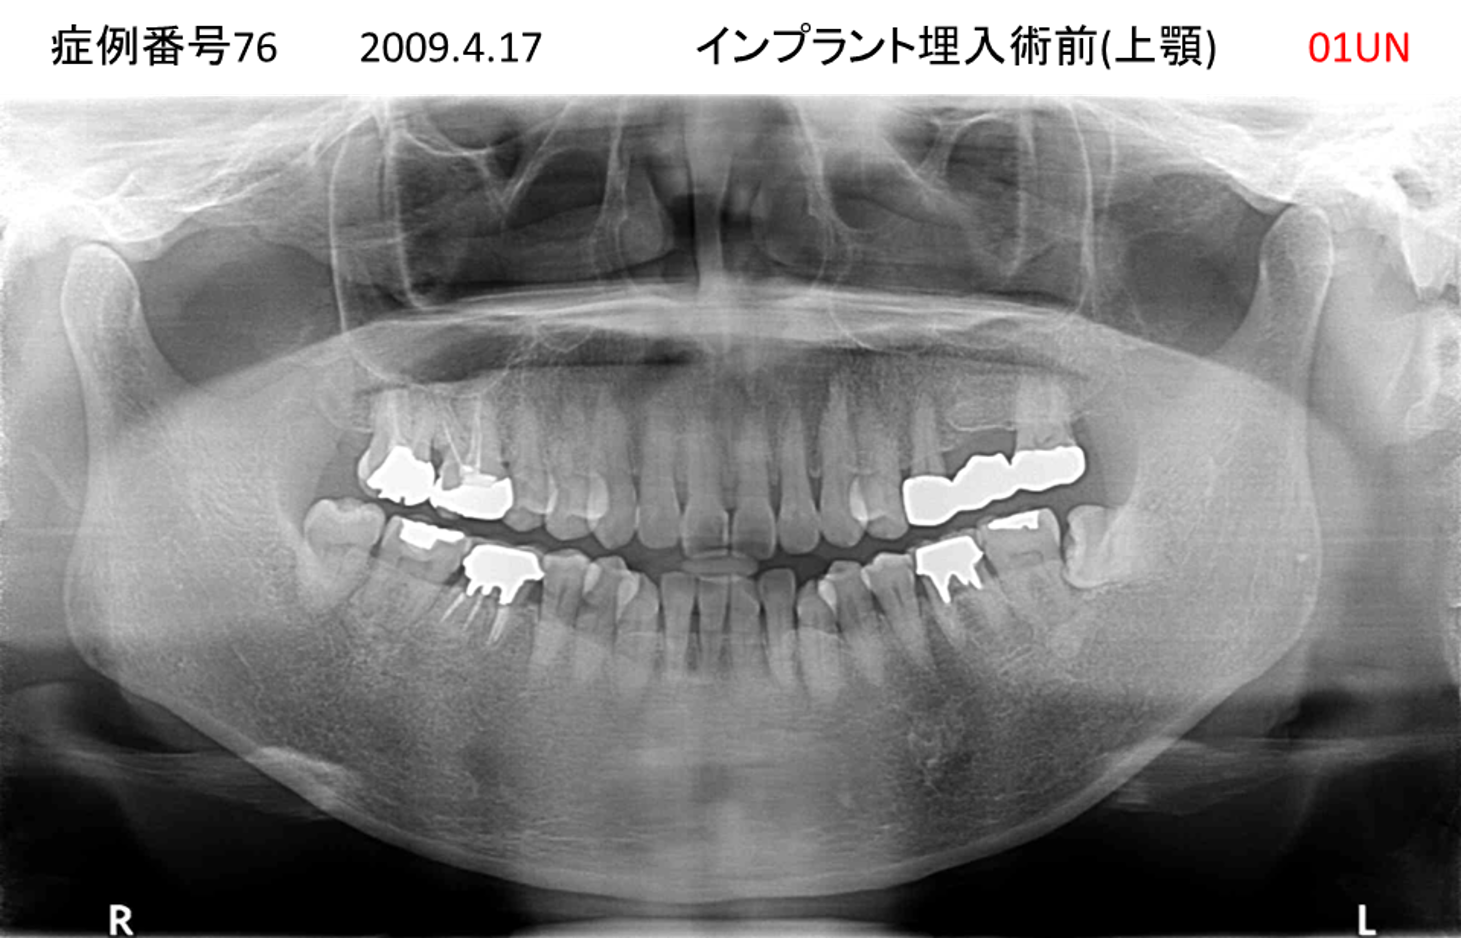

全く噛めない患者様のインプラント症例

| 治療名称 |

インプラントオーバーデンチャー |

| 治療費用 |

520万円+税 |

| 治療期間 |

6か月 |

| 患者さんの症状(主訴) |

全く噛めない。何とかしてほしい |

| 治療内容 |

サイナスリフト、インプラント、義歯作製(ロケーター) |

| 治療結果 |

好きなものが食べられるようになった。見栄えがとても良くなった。 |

| 治療の注意点(リスク/副作用) |

義歯が壊れた場合、インプラントが壊れた場合は再治療が必要 |